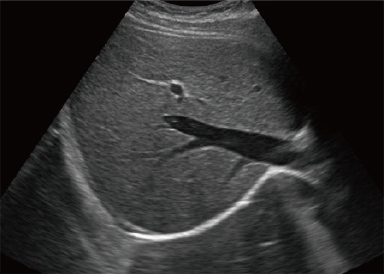

OFF

ON